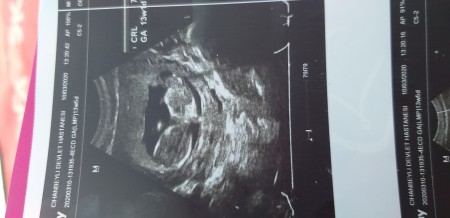

Bebeğim 13 haftalık cinsiyet tahmini yapar misiniz çok merak ediyorum Upload failed: [object Object]

Gebelik haftası 13